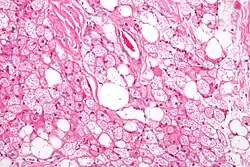

Micrograph of a hibernoma. H&E stain.

The tumors histologically resemble brown fat. There are four histologic types recognized, but one is the most frequently seen (typical). There is a background of rich vascularity.

1. Lobular type: Variable degrees of differentiation of uniform, round to oval cells with granular eosinophilic cells with prominent borders, alternating with coarsely multivacuolated fat cells (pale cells). There are usually small centrally placed nuclei without pleomorphism. The cells have large cytoplasmic lipid droplets interspersed throughout.[4][5]